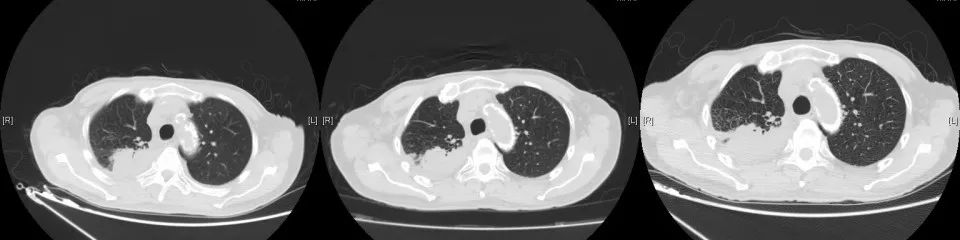

CT变化:

2018年1月复查胸部CT:右肺占位较前增大,余无明显特殊不适。外院再次行肺穿刺活检,病理:右肺组织见癌转移(符合膀胱癌肺转移)。2018年3月14-29日于我院行肺转移灶局部放疗。2018年5月15日-7月11日予标准方案化疗2周期。期间病情稳定。2018年10月复查,局部肺转移灶增大进展、且出现肺新转移灶,评估疗效PD,行NGS全基因检测,根据检测结果,即选用阿法替尼口服行靶向治疗。

2020年3月复查,病灶再次进展,参考前次基因检测结果,结合临床情况,即开始给予口服吡咯替尼80mg每日一次,2020年4月25因心梗住院治疗。停药约2周。复查示原转移灶稍增大,考虑是否与停药有关,故继续维持吡咯替尼治疗。期间多次复查,病情稳定。局部考虑缓慢进展可能。但综合考虑临床情况,仍继续维持原方案治疗。

2021年5月19日常规复查CT考虑多发肝转移,肺原局部病灶稍进展。考虑吡咯替尼耐药,即予停用。即予“替雷利珠”200mg行免疫治疗1次。无明显副反应。2021年6月因肺部感染、合并心衰去世。